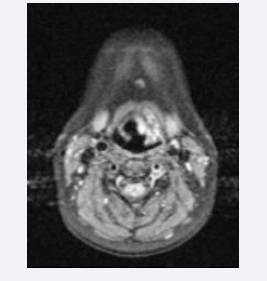

Magnetic resonance imaging (MRI) of the neck revealed a neoplastic lesion in the glottis and supraglottis, more notably on the left, with obliteration of the pyriform sinus and ipsilateral vallecula; anterior commissure and vocal folds bilaterally. No nodular lesions were found in the neck (Figures 4-6).

Axial MRI image showing hemangioma in the left vocal fold

Figure 4: Axial MRI image showing hemangioma in the left vocal fold

Axial MRI showing significant control after the third procedure

Figure 9: Axial MRI showing significant control after the third procedure

The control MRI after the third procedure presented the following report: “Tumor lesion with characteristics of residual and/or recurrent hemangioma. Trachea and infraglottic region without abnormalities (Figures 10,11).